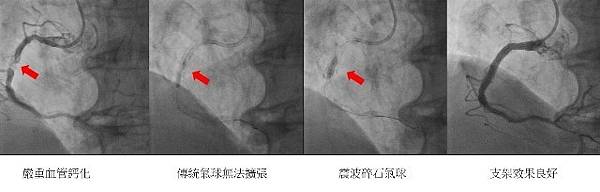

【柿子日報記者李玲/台南報導】「血管鈣化」是心血管疾病中常見的主要挑戰,嚴重鈣化會導致血管狹窄、限制血流,並增加心臟冠狀動脈或周邊動脈阻塞的風險。而傳統治療手段(如氣球擴張或鑽石旋磨術)在處理深層鈣化時可能效果不佳,甚至有血管破裂等高風險的併發症;此時,血管內震波碎石術(Intravascular Lithotripsy,簡稱IVL)便成了較適合患者的新選擇。

安南醫院心臟內科醫師林霈說明,IVL的技術靈感來自腎結石的震波碎石術,透過特製導管在低壓下釋放聲波震動,能夠高效地「震碎」深層與表層的鈣化斑塊,使血管擴張更完全並恢復通暢。她進一步指出IVL的3大核心優勢:

林霈醫師分享,安南醫院近期已有3位血管嚴重鈣化患者受益於IVL技術:兩位患者過去曾接受鑽石旋磨術來處理嚴重鈣化斑塊,但因為鈣化病灶太厚,因此仍無法完全擴張血管;另一位患者則是經氣球擴張術後,未能有效撐開鈣化病灶,綜合考量其風險較高,故未進一步執行鑽石旋磨術。

所幸,上述3位患者在接受IVL技術後,鈣化斑塊皆得以順利震碎,促使血管成功擴張並成功植入支架,進而恢復正常血流。林霈醫師補充,IVL技術能夠協助醫師有效處理以往極具挑戰性的鈣化病例,且在改善患者的血管健康之餘,還能顯著減少風險。若民眾也有嚴重血管鈣化之相關困擾,她建議及早就診,與醫師討論最適合自己的手術方案。